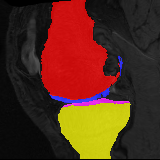

Image

Manual Seg

DA-1

Mono-21

DA-21

Mono-65

Knee MRI experiment: We test our method on 3D knee MRIs from the Osteoarthritis Initiative (OAI) 111https://nda.nih.gov/oai/ and corresponding segmentations of femur and tibia as well as femoral and tibial cartilage [1]. From a total of 507 labeled images, we use 200 for training, 53 for validation, and 254 for testing. To test registration performance we use 10,000 random image pairs from the test set. All images are affinely registered to an atlas built from the training images, resampled to isotropic spacing of 1mm, cropped to and intensity normalized to [0,1]. In addition, right knee images are flipped to be consistent with left knees. For training, the loss weights are , , and based on approximate hyper-parameter tuning. Note that when computing from the displacements, the image coordinates are scaled to [-1, 1] for each dimension following the convention in the interpolation function of PyTorch.

Results: All trained networks are evaluated using Dice overlap scores between predictions and the manual segmentations for the segmentation network, or between the warped moving segmentations and the target segmentations for the registration network. Tabs. 1 and 2 show results for the knee and brain MRI experiments respectively in Dice scores (%). Fig. 2 shows examples of knee MRI registrations and brain MRI segmentations.

Qualitative results: DA achieves more anatomically consistent registrations than the mono-networks on the knee (Fig. 2) and Brain MRI samples (see supplementary material).